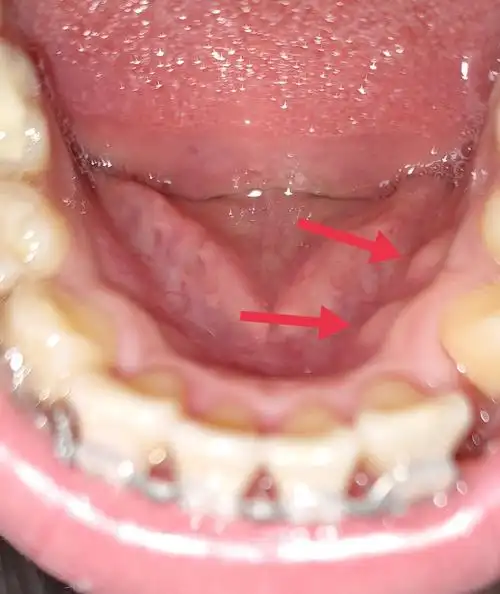

牙龈增生